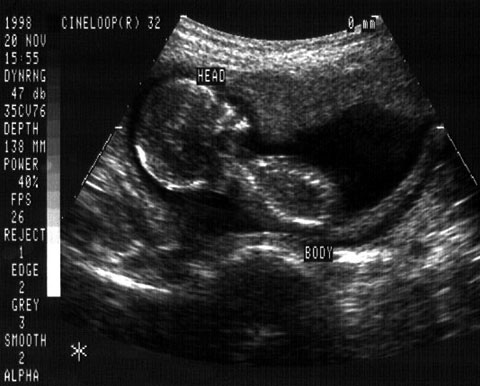

Schwangerenvorsorge und Missbildungsdiagnostik

Die Schwangerschaftsvorsorge wird nach den üblichen Mutterschaftsrichtlinien durchgeführt.